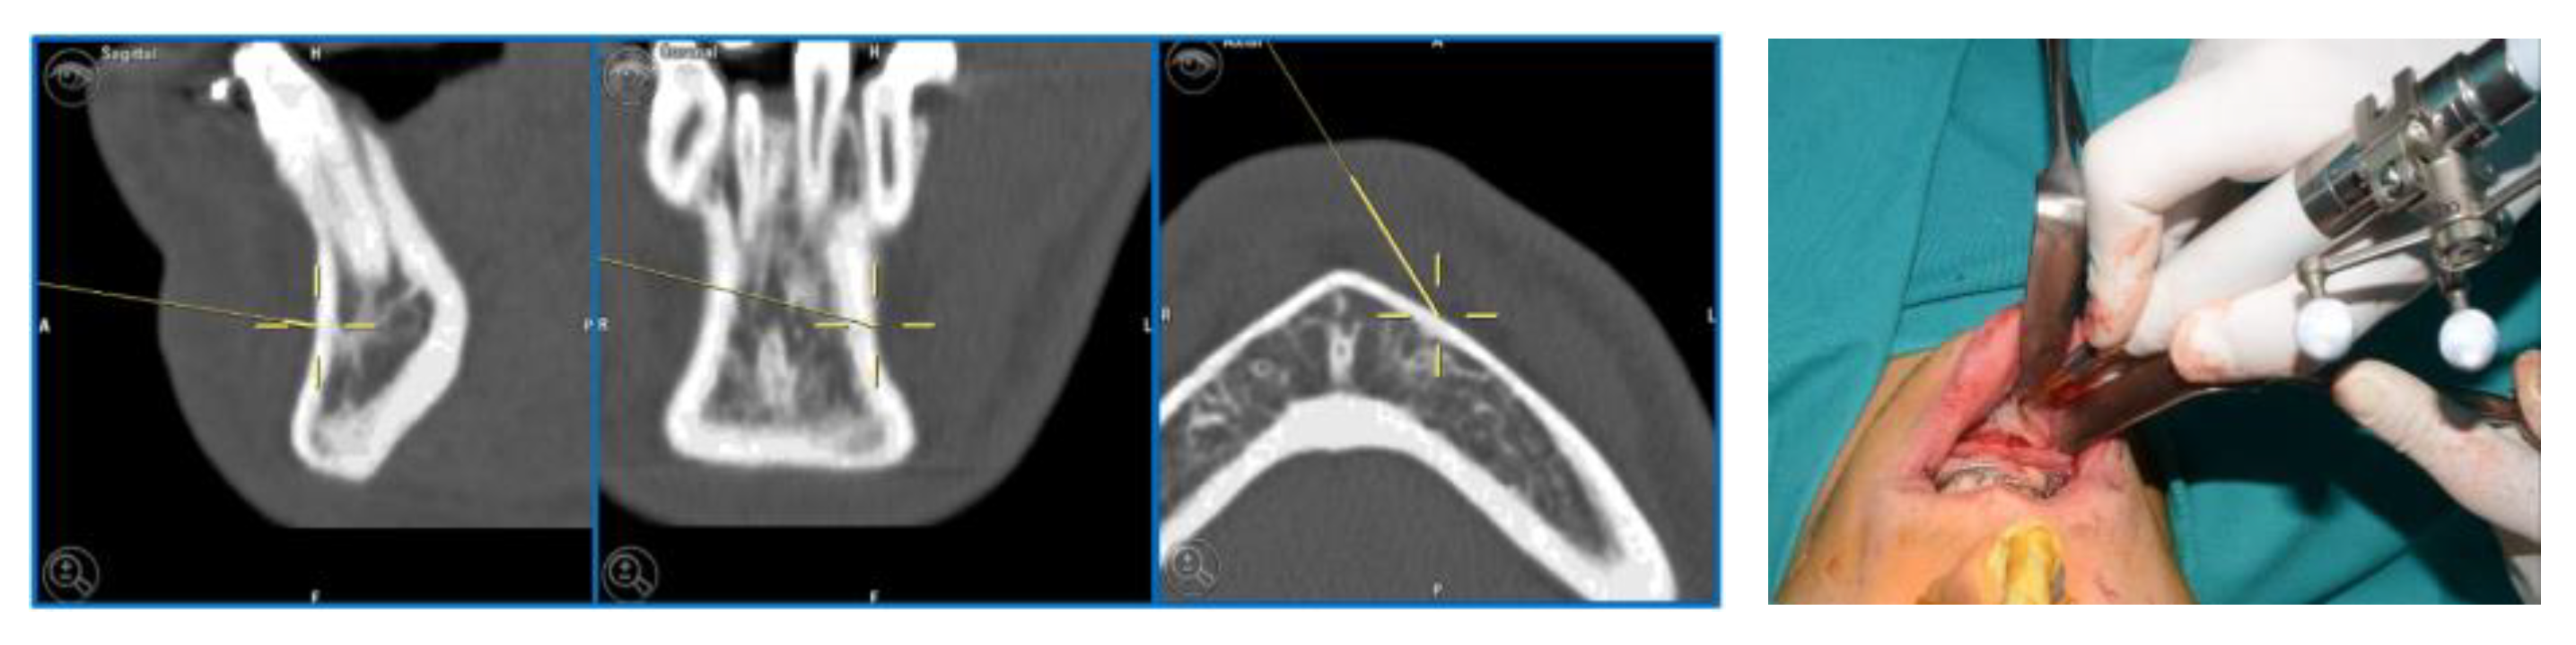

5. CASE 3: Subapical (Köle) Osteotomy in Dento-Facial Deformity

A 23-year-old patient exhibited a class III dentoskeletal malocclusion, as well as transverse and sagittal hypoplasia of the upper maxilla. Moreover, the patient presented an inclination of the teeth in the anterior mandibular sector that could not be orthodontically treated. Consequently, the following treatment plan was formulated:

- First step: SARPE (Surgical Assisted Rapid Palatal Expansion) and subapical (Köle) mandibular osteotomy, followed by subsequent distraction osteogenesis.

- Second step: LeFort I maxillary osteotomy segmented into two pieces.

For the subapical osteotomy, it was decided to use the tracked tool technique with a piezoelectric scalpel to perform the procedure and avoid the risk of dental root injury, thereby enhancing surgical precision. A maxillary bite was created, and 5 screws with different space vectors were then placed on it, serving as fiducial markers. The bite was used to ensure that, during the entire surgical procedure, the mandible maintained the same position as in the preoperative CT scan. Virtual planning was performed with careful consideration of dental root preservation in the osteotomy tracing. During the surgical procedure, the Dynamic Reference Frame (DRF) was positioned in the left parietal bone, and the screws located on the bite were used as fiducial markers. The same bite used during the acquisition of CT scan images was used. Two screws were secured onto the maxillary bone, with an additional one in the mandibular symphyseal region. Simultaneously, an intermaxillary fixation was used to replicate as accurately as possible the mandible’s position maintained during the CT scan image acquisition (Figure 8).

The piezoelectric tool was registered by anchoring the three reflective spheres to the tool’s handpiece. At the same time, the tip of the piezoelectric device was marked and used as a reference for navigation (Figure 9).

The navigation accuracy was less than 1 mm. The subapical osteotomy was performed as previously planned (Figure 10).

Figure 10.

Surgical navigation and Subapical osteotomy (Köle) with tracked piezoelectric device.